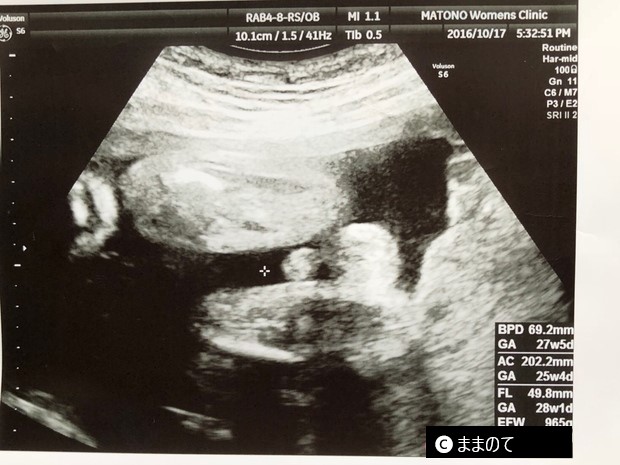

【男の子のエコー】妊娠26週

写真中央付近の+マークの右側に、突起物と袋がはっきり見えます。突起物と袋のセットで確認できれば、奇形や異常の場合を除き、男の子である確率はほぼ100%です。